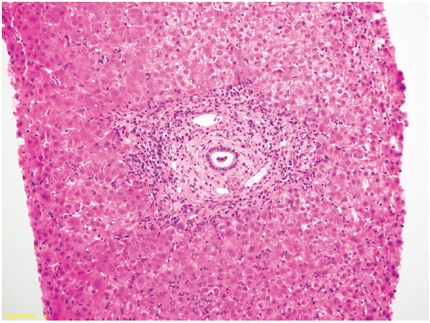

Histológicamente, se caracteriza por edema celular o balonización, necrosis aislada con formación de cuerpos acidofílicos o necrosis masiva acompañada de agregados de neutrófilos y colestasis hepatocanalicular de localización perivenular (zona 3), dada la mayor susceptibilidad de esta región a los eventos isquémicos, los cambios se hacen evidentes en las primeras 48 horas después del trasplante (Figuras 1 y 2). Cuando se toman biopsias en tiempo cero (0), o posreperfusión, son más prominentes los agregados de células inflamatorias polimorfonucleares neutrófilos. En casos severos, disminuye la inflamación y aumenta la necrosis, lo que compromete todo el ácino (panacinar) (13).

Menos frecuentemente pueden observarse necrosis en región periportal o infartos subcapsulares. Cuando hay donante con hígado graso, la lesión de reperfusión favorece la ruptura de hepatocitos, lo que libera glóbulos de grasa, que se quedan atrapados en los cordones de hepatocitos y causan obstrucción, semejando sinusoides dilatados o lipopeliosis, los cuales pueden migrar al pulmón causando embolia grasa. El pronóstico de esta condición depende directamente del porcentaje de parénquima con necrosis (14). Se incluyen en el diagnóstico diferencial el rechazo humoral, rechazo celular y complicaciones quirúrgicas, en especial de anastomosis vascular o de la vía biliar. La colestasis de presentación muy temprana también puede deberse a injertos pequeños para el donante (small-for-size), casos en los que el edema celular es muy prominente y de localización no solo perivenular sino que puede ser difusa o panacinar.